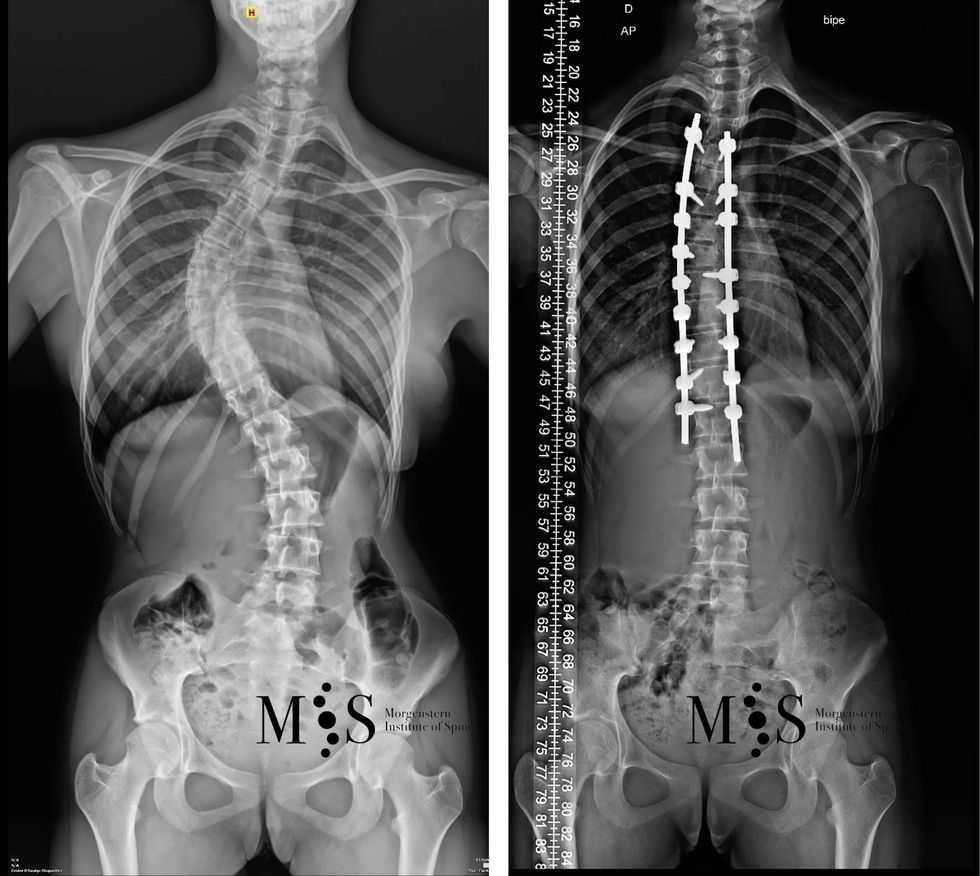

4. Klasifikimi në bazë të këndit të kurbës (këndi i Cobb-it)

• Skolioza e lehtë: Kur këndi është më i vogël se 25 gradë.

• Skolioza mesatare: Kur këndi është midis 25 dhe 40 gradë.

• Skolioza e rëndë: Kur këndi është mbi 40 gradë.

Klasifikimi ndihmon mjekët të vendosin trajtimin më të përshtatshëm për pacientët, përfshirë terapi fizike, mbajtës (korrektorë) ose, në raste ekstreme, kirurgji.

Për të trajtuar skoliozën, është e rëndësishme të bëhet një diagnozë e hershme dhe të zhvillohen strategji për të menaxhuar sëmundjen. Në raste të lehta, mjafton monitorimi dhe ushtrime për të përmirësuar forcimin e muskujve dhe mbajtjen e një posture të duhur. Kur skolioza është më e rëndë, mund të kërkohen pajisje mbështetëse si korset ose, në disa raste, ndërhyrje kirurgjikale për të korrigjuar deformimin e shtyllës kurrizore. Prandaj, është thelbësore që individët të jenë të vetëdijshëm për këtë çrregullim dhe të kërkojnë trajtim në kohën e duhur.